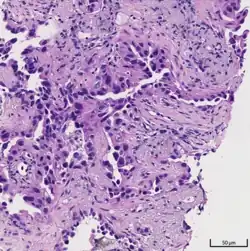

Histopathology of lepidic predominant adenocarcinoma.

Histopathology

Adenocarcinoma of the lung tends to stain mucin positive as it is derived from the mucus-producing glands of the lungs. Similar to other adenocarcinoma, if this tumor is well differentiated (low grade) it will resemble the normal glandular structure. Poorly differentiated adenocarcinoma will not resemble the normal glands (high grade) and will be detected by seeing that they stain positive for mucin (which the glands produce). Adenocarcinoma can also be distinguished by staining for TTF-1, a cell marker for adenocarcinoma.[29]

As discussed previously, the category of adenocarcinoma includes are range of subtypes, and any one tumor tends to be heterogeneous in composition. Several major subtypes are currently recognized by the World Health Organization (WHO)[1] and the International Association for the Study of Lung Cancer (IASLC) / American Thoracic Society (ATS) / European Respiratory Society (ERS):[30][31][32] lepidic predominant adenocarcinoma, acinar predominant adenocarcinoma, papillary predominant adenocarcinoma, micropapillary predominant adenocarcinoma, solid predominant adenocarcinoma, and solid predominant with mucin production. In as many as 80% of these tumors, components of more than one subtype will be recognized. Surgically resected tumors should be classified by comprehensive histological subtyping, describing patterns of involvement in increments of 5%. The predominant histologic subtype is then used to classify the tumor overall.[2] The predominant subtype is prognostic for survival after complete resection.[33]